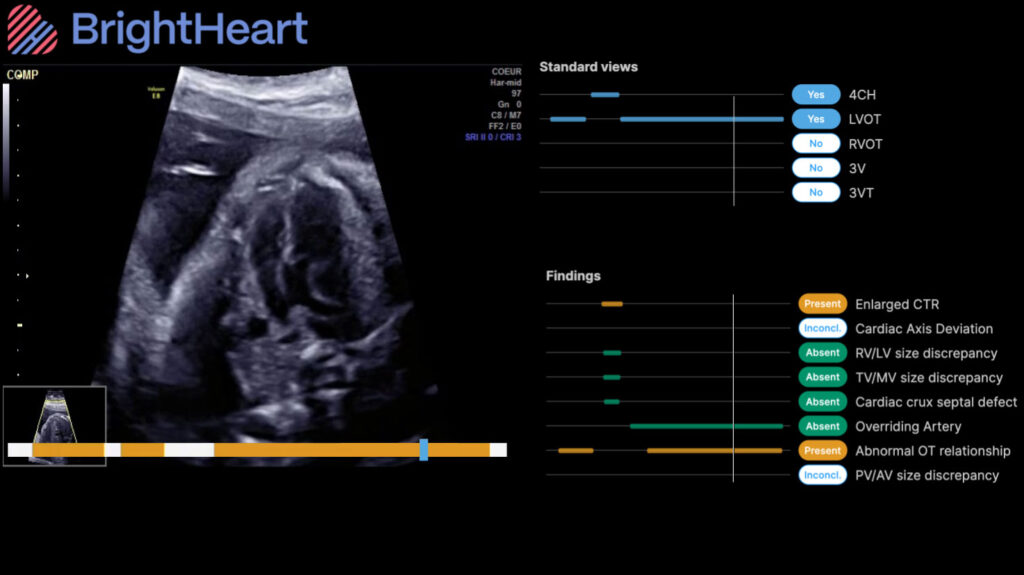

This collaboration combines BrightHeart’s innovative AI technology with GE HealthCare’s trusted Voluson ecosystem through the Voluson Solution Store – the first digital marketplace for Women’s Health ultrasound, available in the U.S. and Europe. Together, the companies are helping to democratize access to expert‑level prenatal care by making clinically validated AI for congenital defect screening and full scan support available to Voluson ultrasound users. Supported by strong clinical evidence – including two recent publications in The Green Journal – and developed with leading fetal cardiology and maternal and fetal medicine (MFM) experts, BrightHeart goes far beyond basic quality checks, delivering reliable, evidence‑backed insights that reduce diagnostic errors and improve the detection of congenital defects while strengthening workflow efficiency. BrightHeart’s AI Platform enhances Voluson’s offering with a simple, intuitive, cloud-based solution that supports enhanced care spanning acquisition, interpretation, and review across care settings and workflows.

Currently, more than 30% of congenital defects go undetected prenatally, and the U.S. is facing both a significant sonographer shortage as well as a growing number of care deserts. Studies show that structural anomalies are identified in up to 6% of pregnancies, making ultrasound a critical opportunity to inform diagnosis and care planning. Yet consistent image acquisition and interpretation remain variable, especially in resource-constrained environments. By providing BrightHeart’s clinically validated AI to GE HealthCare’s trusted Voluson customers, this collaboration facilitates clinician access to expert-level support on their Voluson ultrasound. It empowers OB/GYNs and MFMs to perform more complete, confident exams, leading to greater consistency, earlier clarity, and smarter prenatal care at scale.

BrightHeart has already demonstrated significant benefit with its platform, not only improving screening capabilities and reducing errors, but also improving workflow by improving scan completeness, saving time, and increasing confidence.